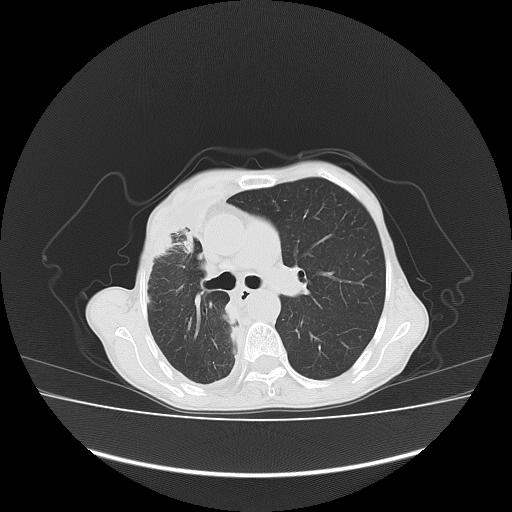

标题: CT16930:女 59 胸痛6个月 胸水脱落细胞学见瘤细胞 [打印本页]

标题: CT16930:女 59 胸痛6个月 胸水脱落细胞学见瘤细胞

可见多发肺内病灶,且胸膜病灶较多有圆球状而非丘状,多考虑胸膜转移瘤伴胸腔积液,右侧胸廓缩小固定,且部分病灶呈丘状,尚不除外恶性胸膜间皮瘤伴肺内转移

右侧胸膜增厚,局部呈结节状增厚,右侧胸腔少量积液。双肺未见确切肿块影。纵隔未见淋巴结肿大。气管、支气管通畅。考虑右侧胸膜间皮瘤(恶性?)可能性大。不除外癌性胸膜炎。

恶性胸膜间皮瘤伴肺内转移可能性大;或胸膜、肺内均为转移瘤,左肺下叶亦见多发小结节影。

右侧胸廓塌陷,右侧胸膜广泛增厚并见多发胸膜结节,右侧少量胸腔积液并包裹。

右胸腔结节均考虑来自胸膜(部分来源于叶裂),考虑胸膜间皮瘤或转移瘤.